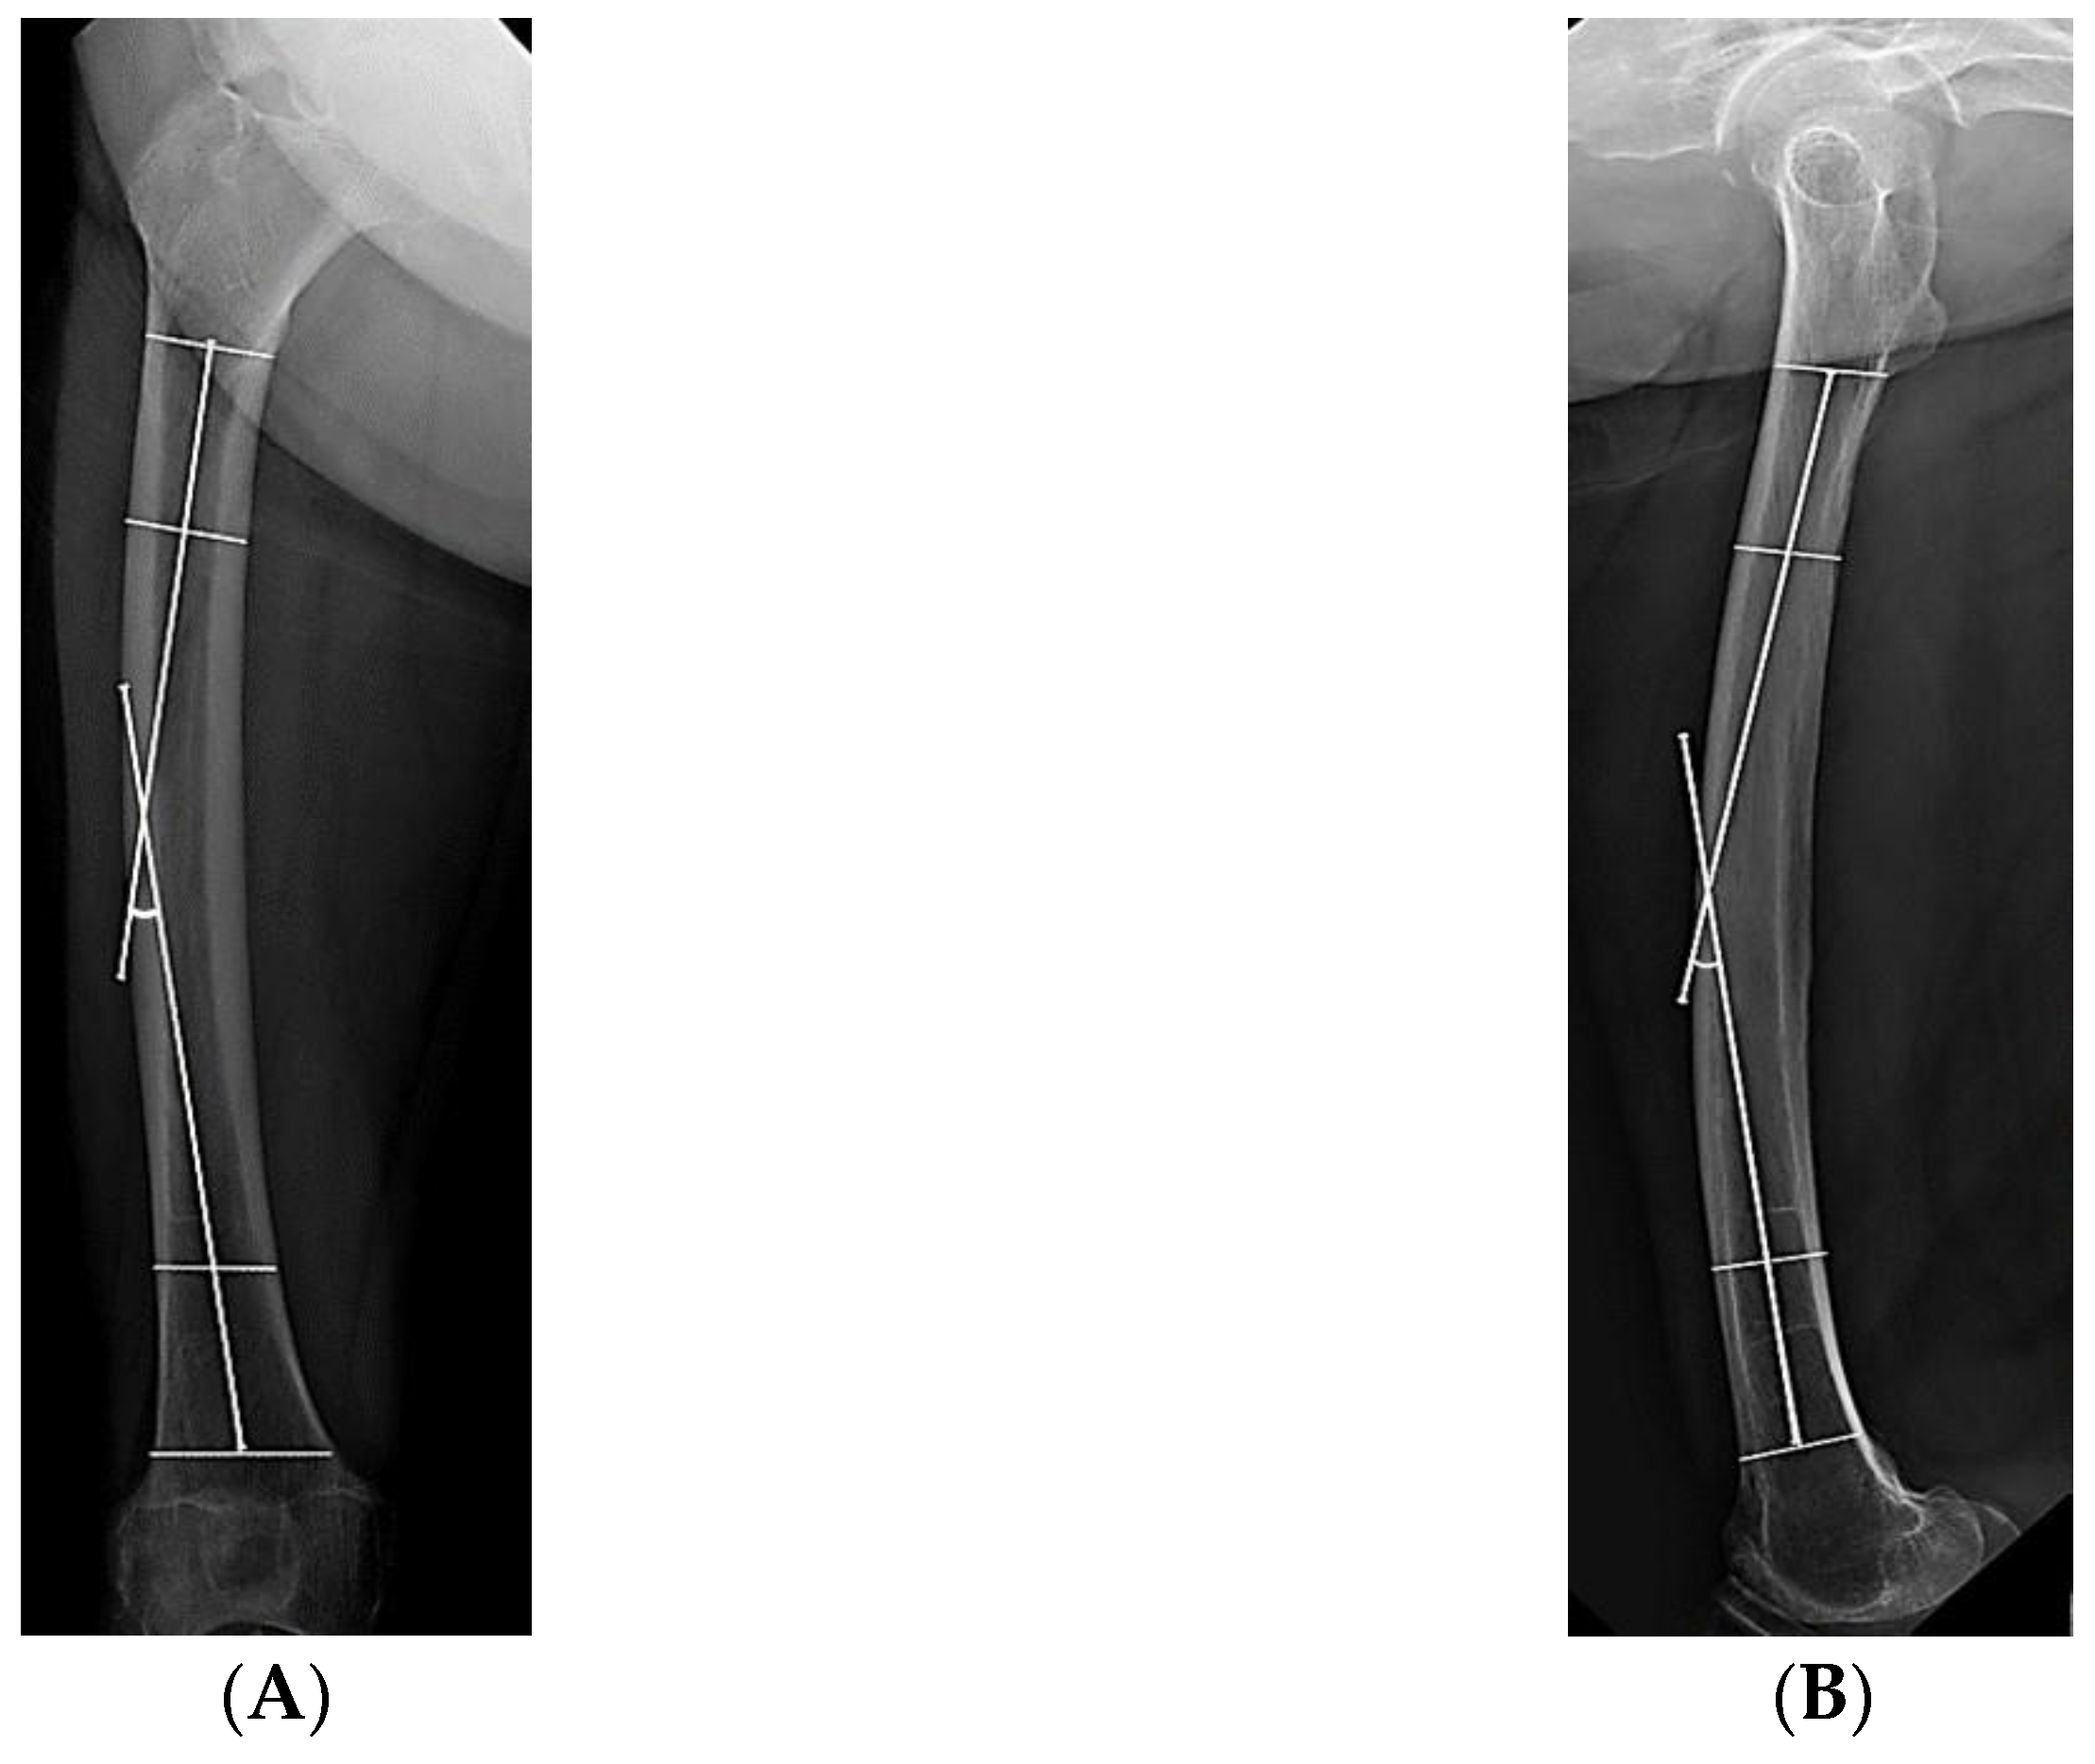

| Lateral bowing, ° | 14.7 ± 5.9 (2.4–24.8) | 7.9 ± 6.5 (0.2–21.9) | <0.001 b |

| Anterior bowing, ° | 16.6 ± 4.2 (9.7–25.1) | 13.0 ± 7.8 (1.0–29.5) | 0.008 b |